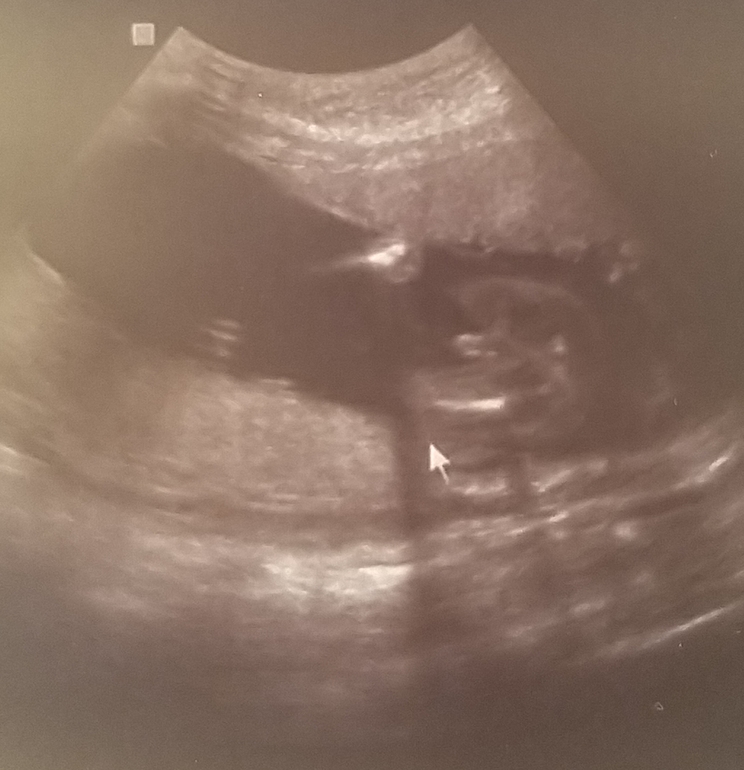

УЗИ в 18.5 недель( фото со стороны попки)